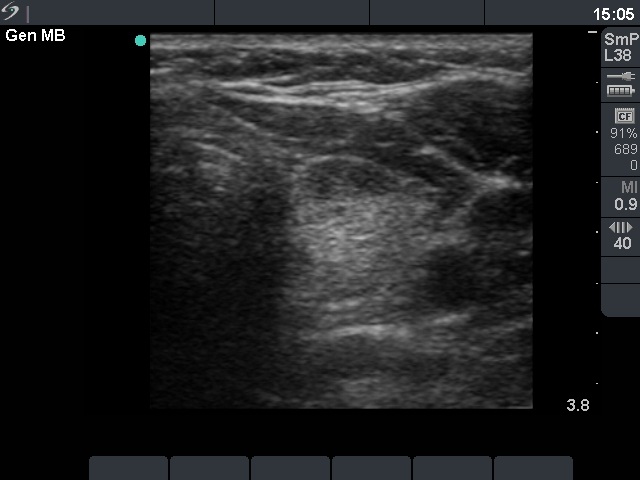

Ultrasonography: the thyroid was echonormal. Several small hypoechogenic lesions were found in both lobes. The dimensions of the largest lesion were 8x4x11 mm. These circumscribed lesions did not fit a nodule.